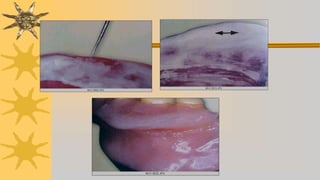

Para detectar posibles zonas de presion ede dentadura sobre

mucosa, se prepara pasta a base de oxido de zink – vaselina y se

pincela parte interna de dentadura

Tambien puede hacerse con silicona fluida

Otros marcan en mucosa inflamada con lapiz y asientan dentadura,

en esta saldrá zona marcada de contacto para hacer desgaste